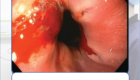

Nội soi trực tràng – phương pháp tầm soát ung thư đại trực tràng ưu việt nhất hiện nay

Nội soi đại tràng gây mê: có thể giúp phát hiện ung thư và cả các dấu hiệu tiền ung thư, các tổn thương lớn nhỏ trong toàn bộ khu vực đại trực tràng.